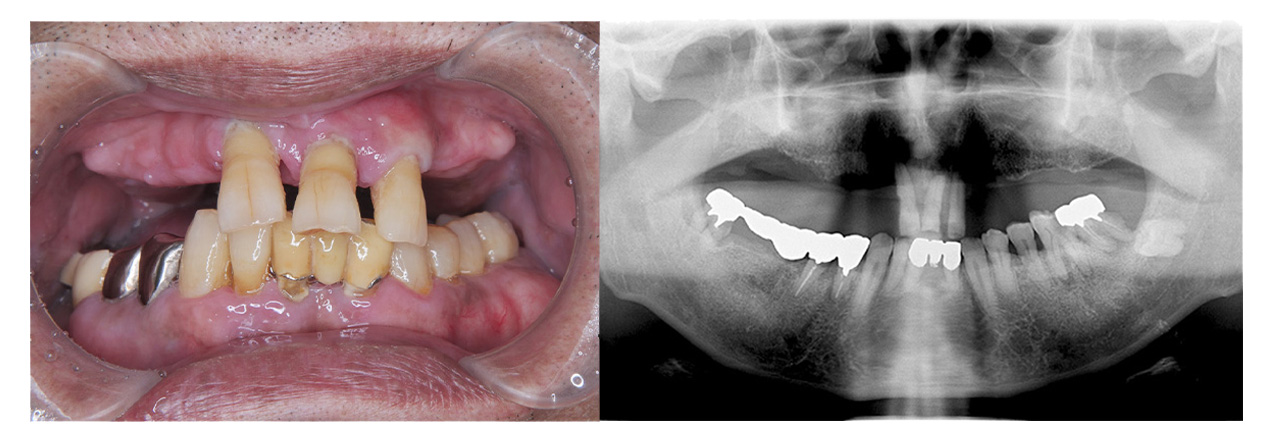

症例その1オールオン4

• Before

• After

咀嚼、審美障害。歯周病でグラグラな歯を全部抜歯してオールオン4で治療した症例。